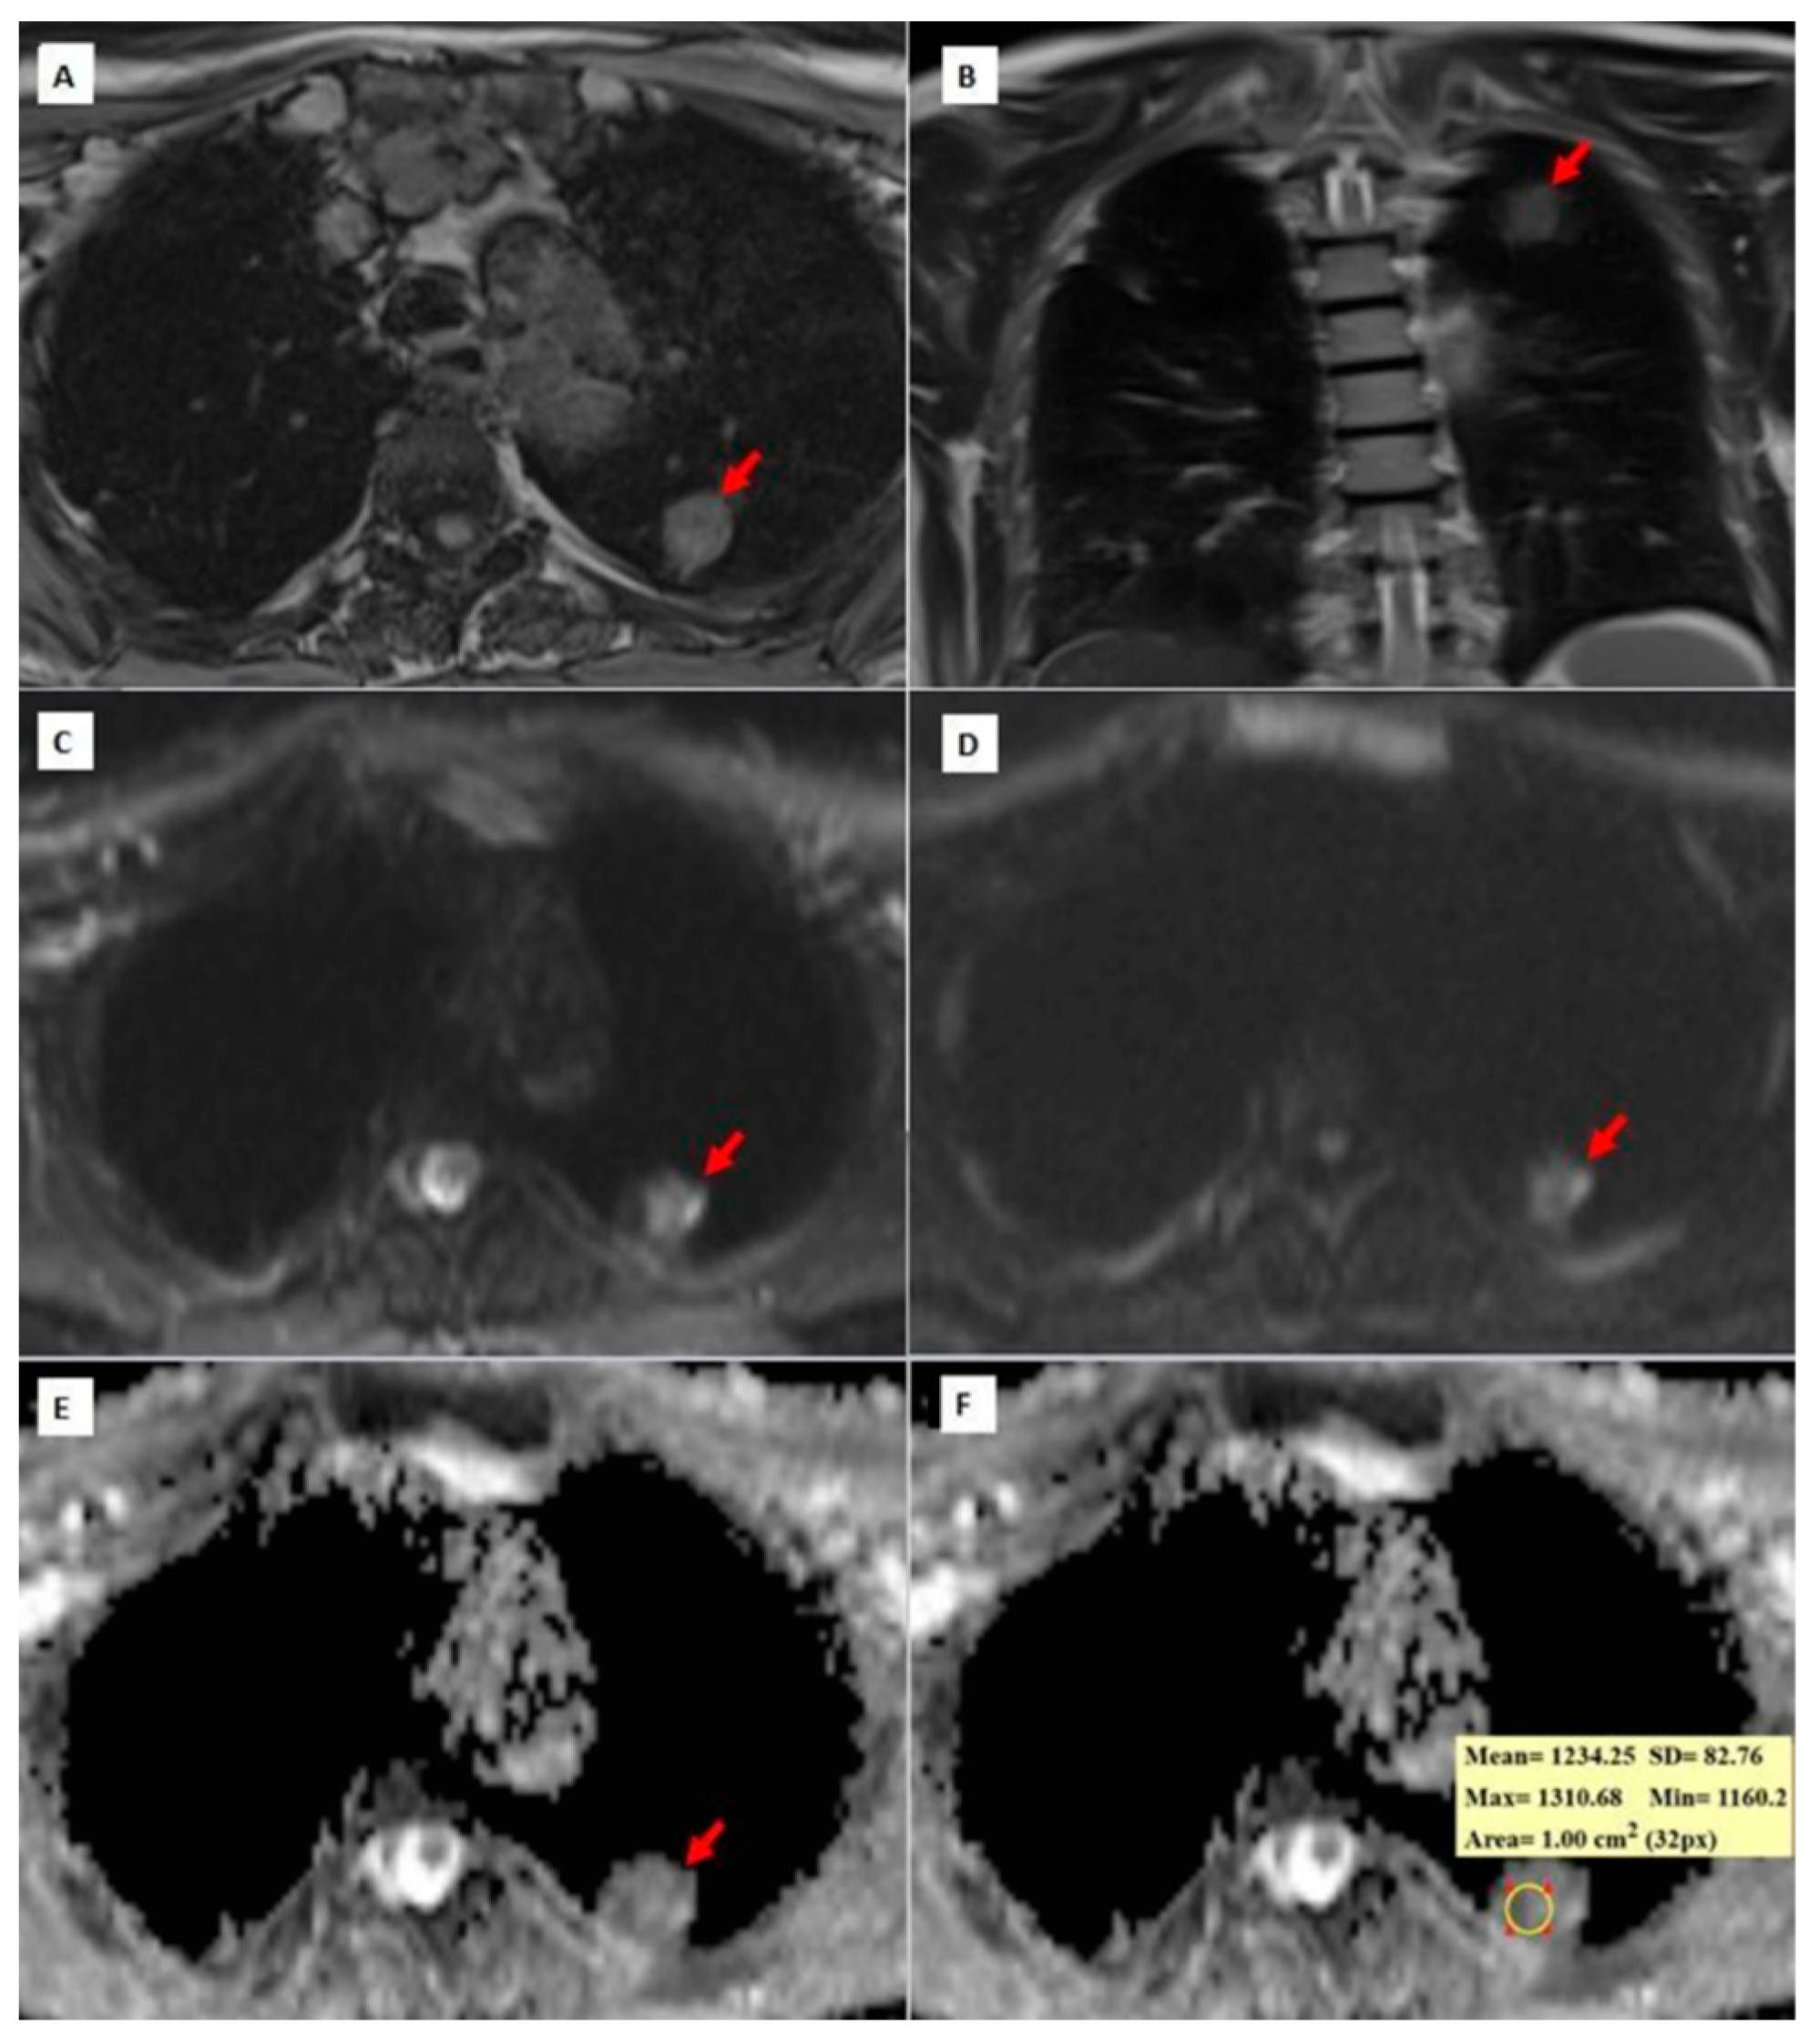

Figure 3, Figure 4 and Figure 5 show thorax MRI images of patients with tumors in the grade 1, 2, and 3 categories, respectively.

Figure 4. A 62-year-old patient diagnosed with grade 2 squamous cell carcinoma. (A) An axial T1W image showing an isointense, round-shaped lung nodule with a slightly spiculated extension towards the pleura in the upper lobe of the left lung. (B) A coronal T2W MRI image showing an isointense left upper lobe lung nodule (red arrow); (C,D) b = 0 and b = 800 DW images, respectively. In the b = 0 DW images, the nodule has a heterogeneous internal structure and there is a more hyperintense area on the left side of the lesion. In the b = 800 DW images, it is seen that the signal of the lesion decreases slightly and the left side remains more hyperintense than the lesion. (E,F) ADC maps showing a hypointense nodule and a mean ADC value of 1234.25 × 10−6 mm2/s. While placing the ROI for measurement on the ADC maps, the asymmetric signal area on the left side of the lesion was excluded in the DW images in order to prevent the DW parameters from being affected by non-tumor areas, such as necrosis, abscess, etc., within the tumor.